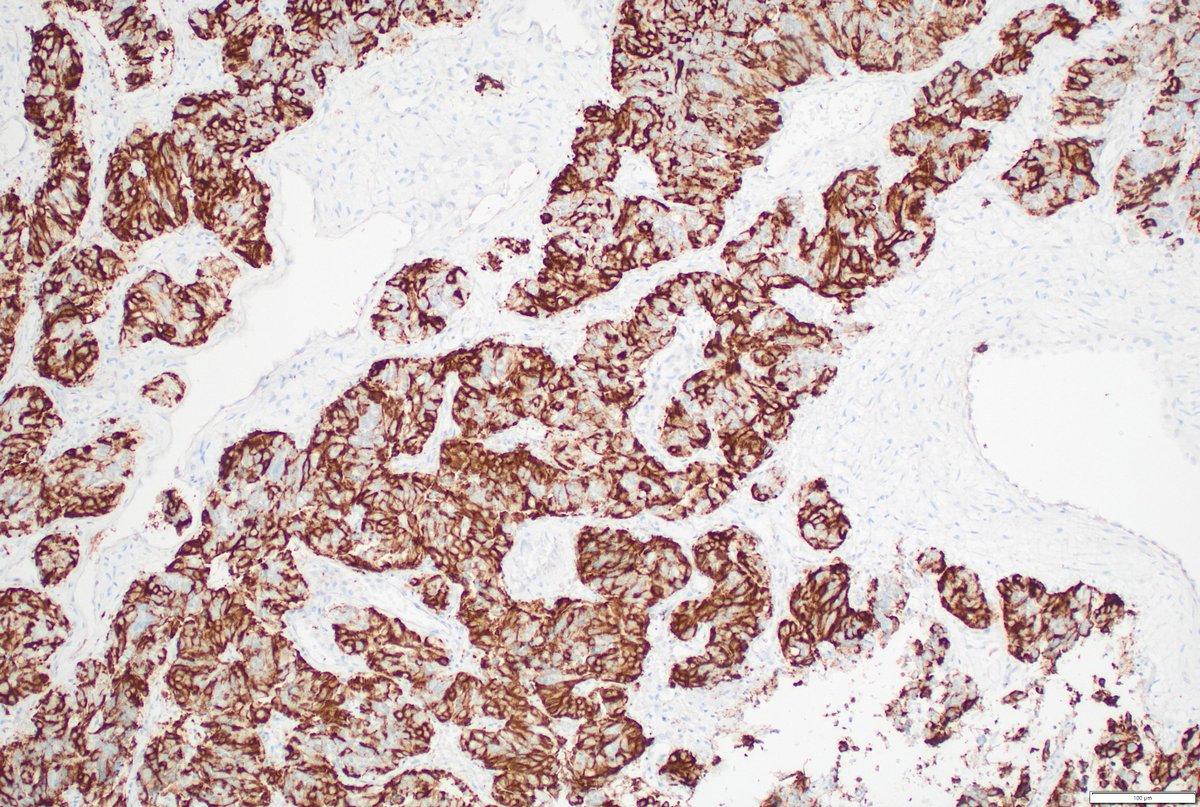

Please consider giving your pathology images a forever home on WebPathology. Now you can load them directly from the site using Submit Images form. Give it a try. Webpathology.com: A Collection of Surgical Pathology Images #PathTwitter #PathX